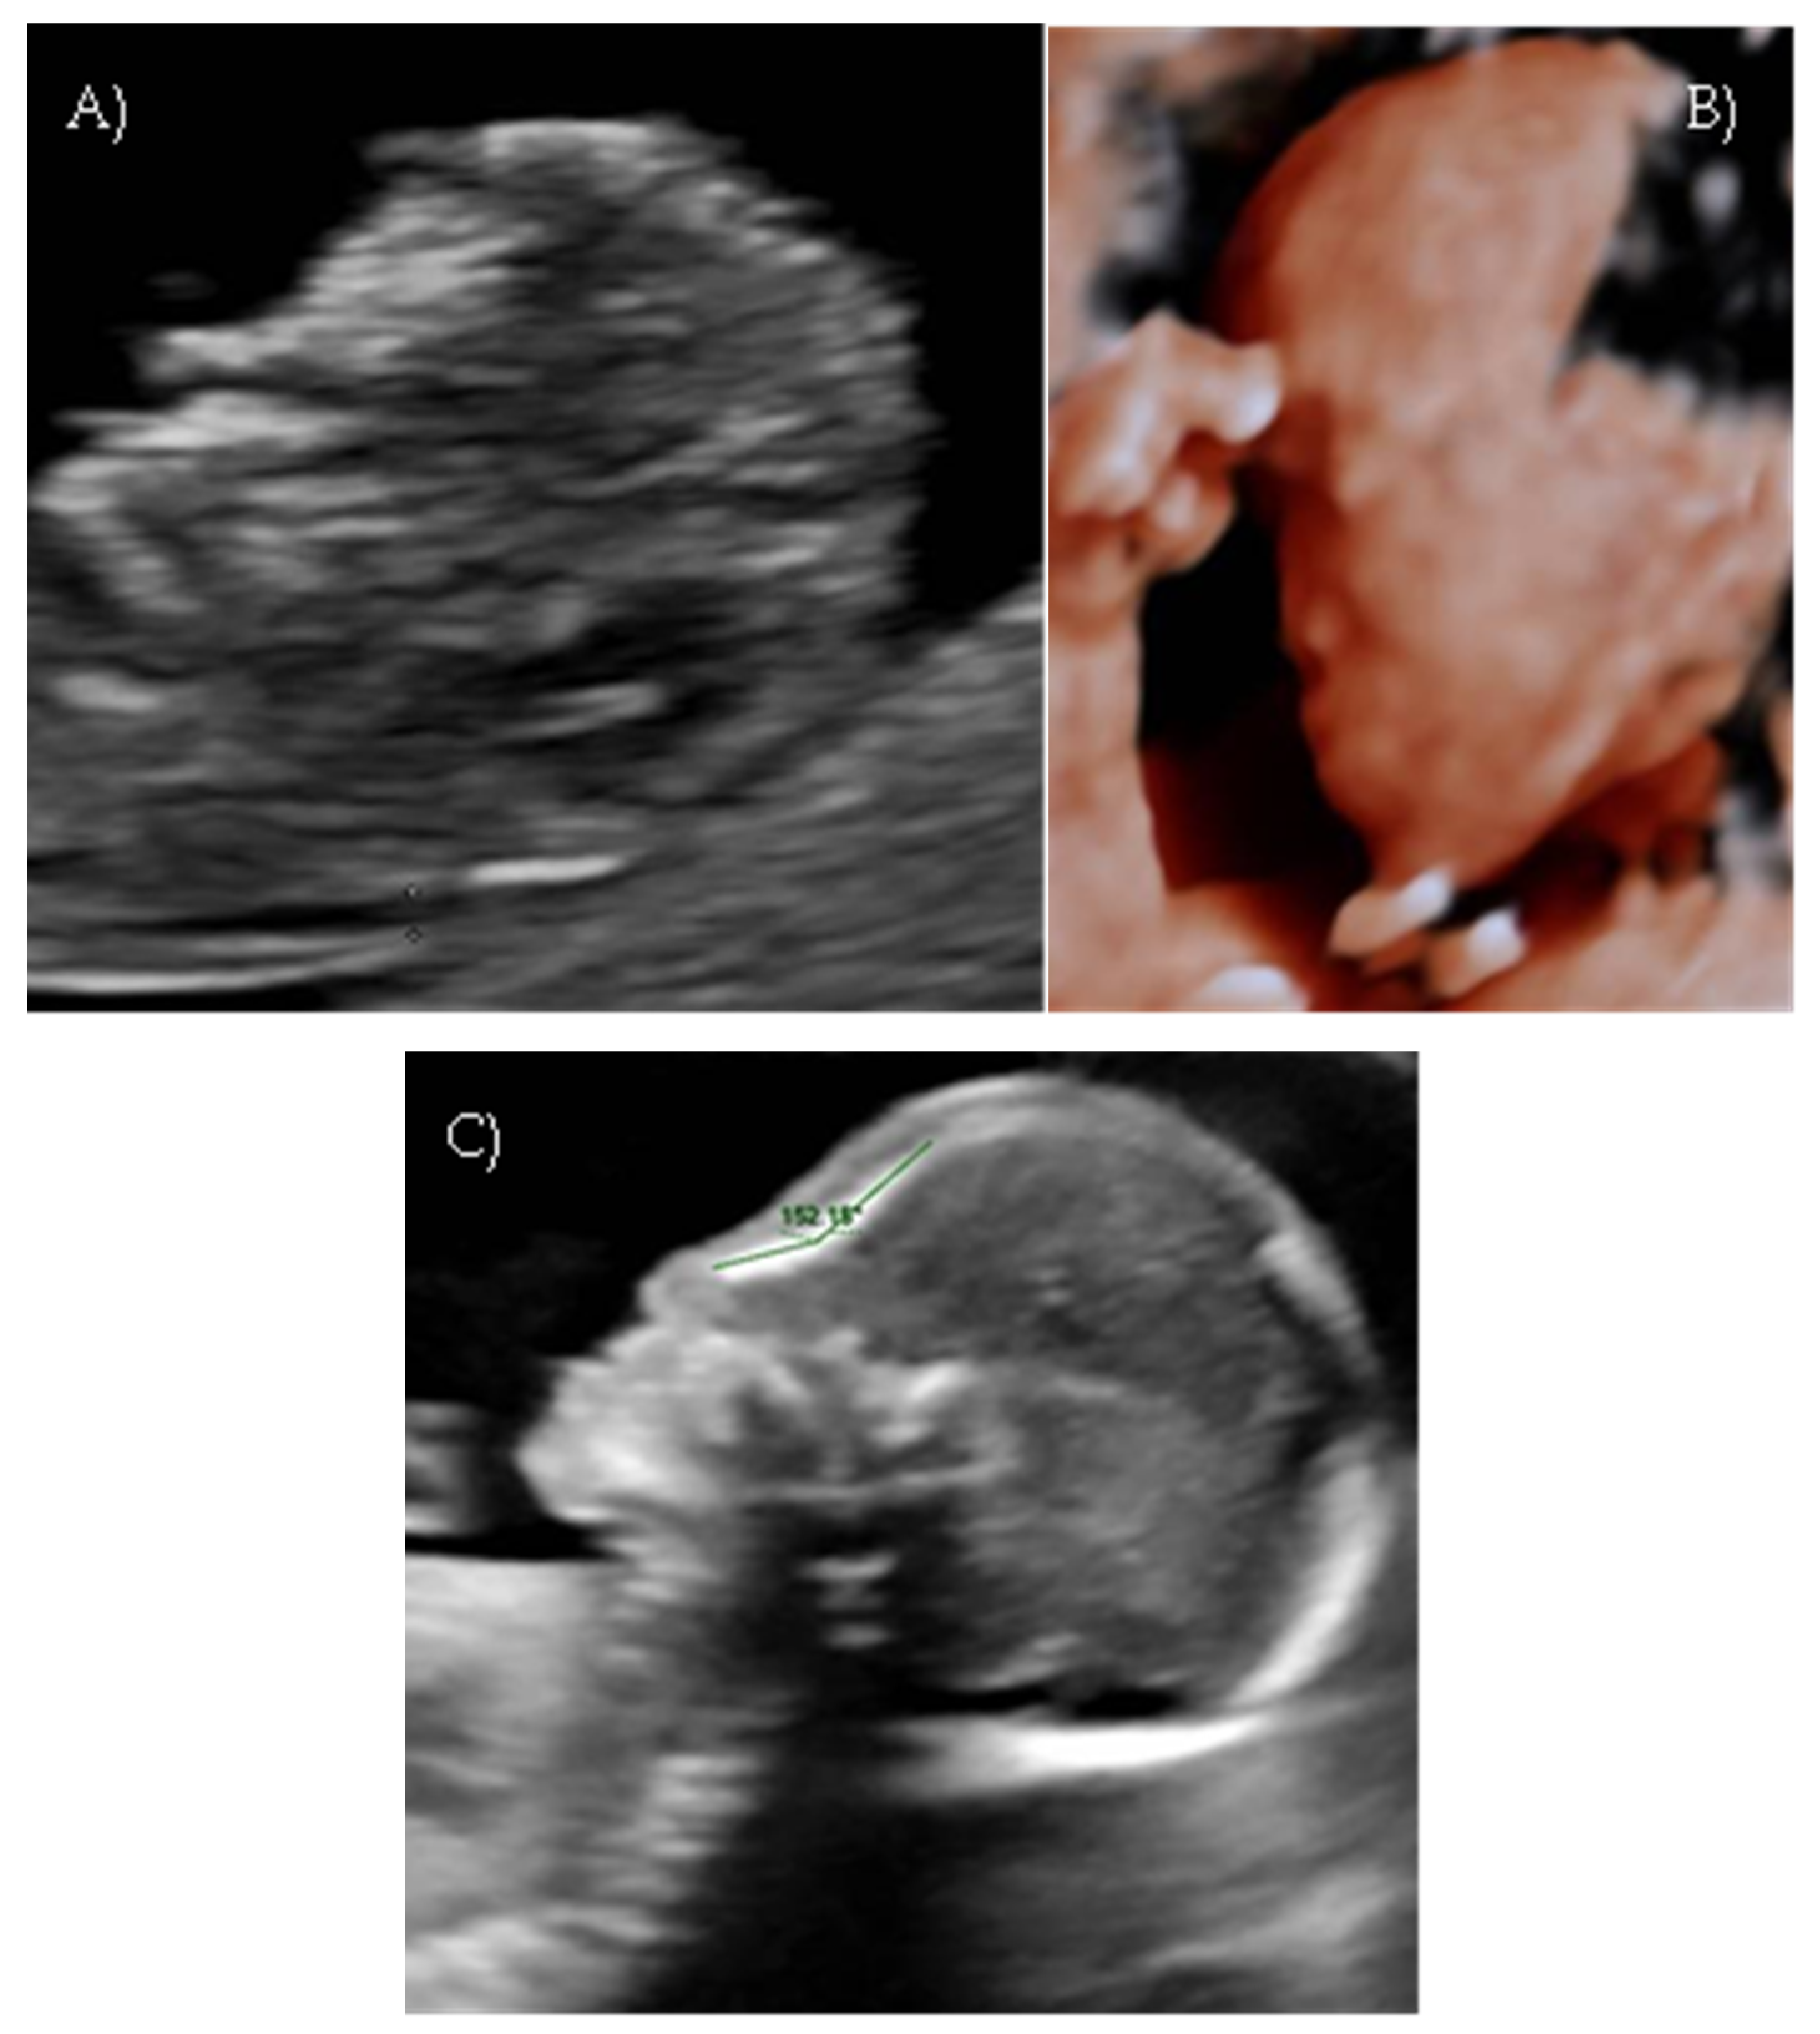

Targeted ultrasound at our center confirmed a flat profile suggestive of Binder-type maxillonasal dysplasia with a nasal-frontal angle of 150,72° (cut-off: <143°), flattening of the curvature of the maxillary alveolar processes (Width: 27 mm, cut-off at 21 weeks: 23.1 mm), short columella, and absent nasolabial philtrum (Figure 5A–D). The remaining fetal anatomy appeared normal.

A targeted anomaly scan at our fetal medicine unit revealed a flat and dysmorphic fetal facial profile with verticalization of the nasal bone, increased NFA, and short columella, suggestive of BP. An associated feature was polyhydramnios. The ultrasound findings were suggestive of Binder-type maxillonasal dysplasia (Nasal-frontal angle: 146.32°, cut-off: <143°) such as the flattening of the curvature of the maxillary alveolar processes (Width: 26.53 mm, cut-off at 22 weeks: 23.9 mm) (Figure 6A–D).

Figure 5. Case 5. (A) Flat fetal profile with verticalization of the nasal bone. (B) Nasal-frontal angle: 150.72°. (C) Absent nasolabial philtrum. (D) Flattening of the curvature of the maxillary alveolar processes. Width: 27 mm.

Figure 6. Case 6. (A) Flat fetal profile with verticalization of the nasal bone. (B) Nasal-frontal angle: 146.32°. (C) Absent nasolabial philtrum. (D) Flattening of the curvature of the maxillary alveolar processes. Width: 26.53 mm.